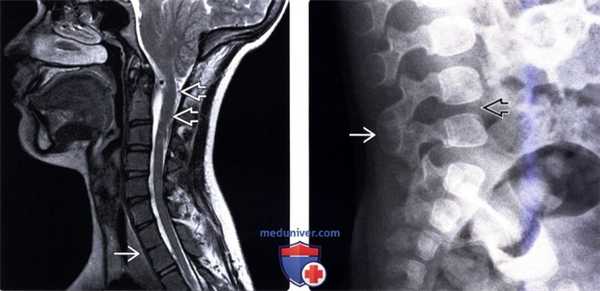

(Слева) Т2-ВИ, сагиттальная проекция (мальформация Киари 2): характерные признаки мальформации задней черепной ямки с дислокацией червя мозжечка ЕЯ в верхнюю часть спинномозгового канала и нарушение сегментации С7 и Т1, у которых помимо тел отмечается слияние суставных и остистых отростков.

(Справа) Рентгенограмма в боковой проекции: одноуровневое нарушение сегментации остистых отростков и пластинок дуг L4 и L5 позвонков. Межтеловое пространство L4/5 также уменьшено в высоте и гипопластично.